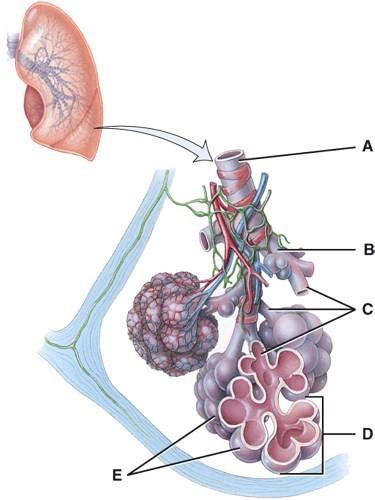

Where is the structure that regulates air flow to the alveolus?

- G

- M

- H

- A

- None of the above

B

What is line J pointing to?

- Right secondary bronchus

- Left secondary bronchus

- Right primary bronchus

- Left primary bronchus

- Carina

D

Where is the right bronchiole?

- F

- G

- H

- L

- M

B

What lines are pointing to tertiary bronchi?

- E and K

- D and J

- F and L

- H and M

- A and B

C

What is line B pointing to?

- Carina

- Visceral pleura

- Parietal pleura

- Pleural cavity

- Diaphragm

C

In this portion of the lungs, the epithelial lining is simple squamous.

- A

- B

- C

- D

- E

E

This is the primary gas exchange structure.

- A

- B

- C

- D

- E

E

What is line C pointing to?

- Terminal bronchiole

- Respiratory bronchiole

- Alveolar ducts

- Alveolar sac

- Alveoli

C

Where is the terminal bronchiole?

- A

- B

- C

- D

- E

A